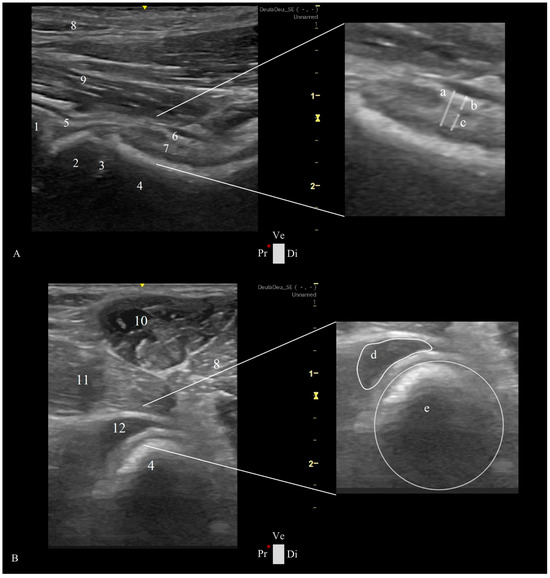

2.3. Ultrasonographic Ventral Hip Joint Approach

- -

- Longitudinal Femoral Head–Neck Plane

- Transverse Femoral Head–Neck Plane

2.4. Ultrasonographic Hip Joint Measurements